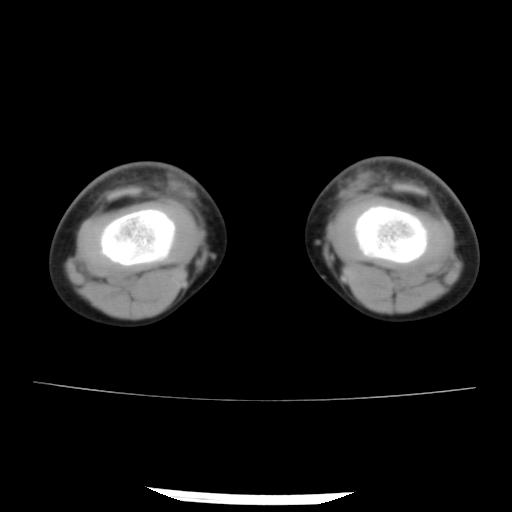

标题: PED0931:男,5岁,发现双小腿软组织肿块1年,质地中等,无 [打印本页]

标题: PED0931:男,5岁,发现双小腿软组织肿块1年,质地中等,无

多发性神经纤维瘤?

考虑多发性神经纤维瘤.